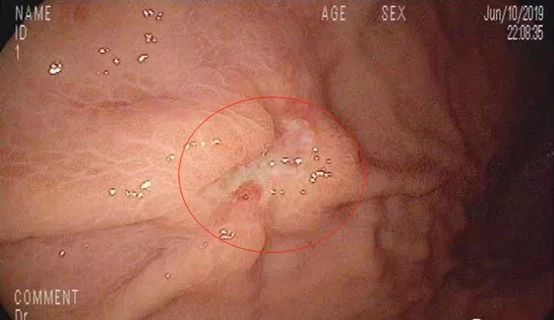

首先发现胃窦黏膜呈鸡皮样隆起,经验告诉我们:胃窦、胃体黏膜呈结节状表现,叫做鸟肌样胃炎或鸡皮样胃炎,它大多与Hp感染有关,清除Hp后结节性胃炎可减轻或消失,但是有发生未分化癌的可能。

随后充分充气,胃腔皱襞完全展开,果然在胃体中部大弯侧近前壁发现一处隆起凹陷型溃疡病变,大小约2x1.5cm,看起来,这就不是什么好东西!

上午9:30,胃镜下病灶处深部取材8块,准备送检做病理检查。

2019年6月14日,活检结果出来了,病理诊断:低分化印戒细胞癌!